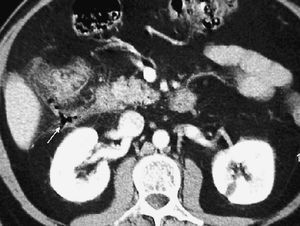

La forma más frecuente es la ausencia de rotación intestinal, que implica importantes alteraciones anatómicas valorables tanto en la ecografía como por la TC. Los principales hallazgos radiológicos son: alteración en la posición del duodeno, que no pasa entre la aorta y la arteria mesentérica superior (AMS); la localización en el hemiabdomen derecho de las asas de intestino delgado y en hemiabdomen izquierdo las de intestino grueso, y una verticalización o inversión de los vasos mesentéricos respecto a su posición normal, quedando la AMS a la derecha y la vena mesentérica superior (VMS) a la izquierda1,2 (fig. 1).

Fig. 1--Malrotación intestinal. (A) y (B) Tomografía computarizada con contraste oral e intevenoso mostrando inversión de la arteria mesentérica superior (AMS) (punta de flecha) y la vena mesentérica superior (flecha). La tercera porción duodenal (D) no cruza la línea media entre la aorta y la AMS, localizándose las asas de yeyuno a la derecha.